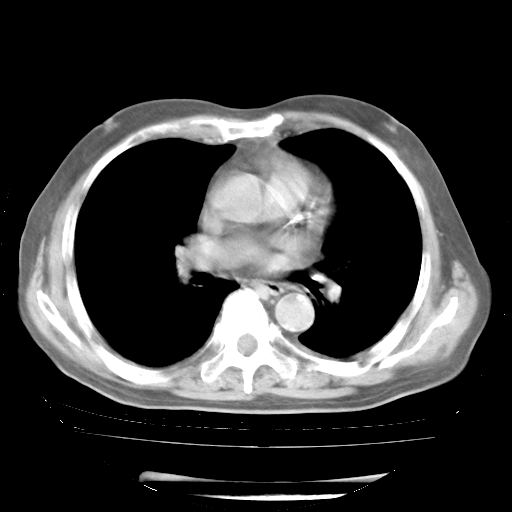

今天部分检查

轻微咳嗽,无痰,(体温正常时)R20次/分,P75次/分,双肺底、腋下可闻及少量捻发音。下肢轻度浮肿。

血常规:白细胞9.11×109/L,N0.92,L5.64,血小板39.2×109/L,HB148g/L,ESR2mm/H。

尿常规:潜血+

血生化:总蛋白69.71g/L,白蛋白38.40g/L,球蛋白31.31g/L,CRP27.9mg/L,尿素氮11.98mmol/L,肌酐106μmol/L,乳酸脱氢酶1099 U/L,肌酸激酶108U/L,CK-MB 61U/L。

腹部B超:胆囊壁增厚,肝、胆、胰、脾、肾无异常,肠系膜淋巴结、腹膜后淋巴结无增大。

ECG:右心室增大

心脏超声检查:无右心室增大。

增加治疗:异烟肼、利福平、乙胺丁醇,静滴左氧氟沙星、参麦注射液。甲强龙从80mg暂减为40mg。

强的松3月1日改为10mg qd,4月1日改为10mg qod。3月份以前的减量过程和环磷酰胺疗程需等明天查看记录(我岳父自己做的记录在他家里)。